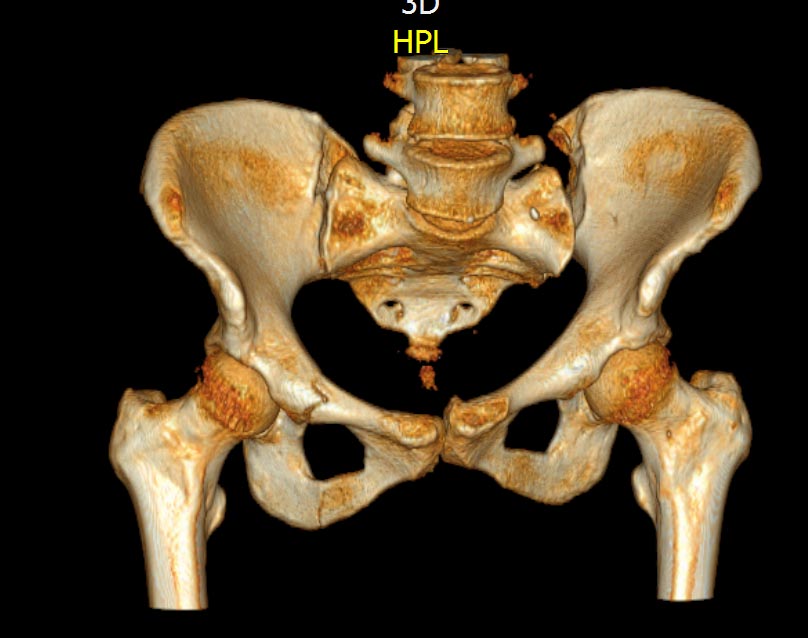

КТ, при детальном рассмотрении виден перелом задних отделов крыла подвздошной кости

KT